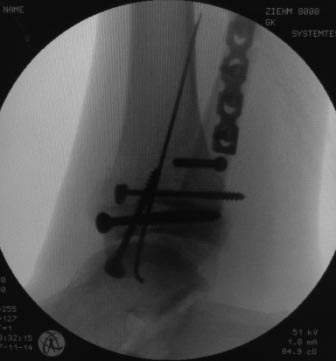

Уважаемые коллеги, всем огромное спасибо за рекомендации. Сегодня

прооперировали. Презервативы в операционной оказались кстати :)

Фото синтеза прилагаю. Качество не ахти, так как фоткал с экрана. Но все

видно.